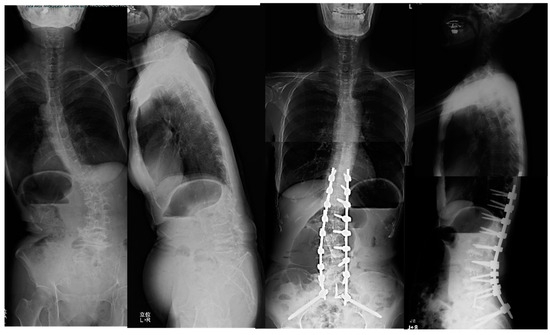

Clinical and Radiologic Analysis of Minimally Invasive Anterior–Posterior Combined Surgery for Adult Spinal Deformity: Comparison of Oblique Lateral Interbody Fusion at L5/S1 (OLIF51) versus Transforaminal Interbody Fusion

by Yoshihisa Kotani, Atsushi Ikeura, Takahiro Tanaka and Takanori Saito

Medicina 2024, 60(1), 107; https://doi.org/10.3390/medicina60010107 - 6 Jan 2024

Background and Objectives: Although adult spinal deformity (ASD) surgery brought about improvement in the quality of life of patients, it is accompanied by high invasiveness and several complications. Specifically, mechanical complications of rod fracture, instrumentation failures, and pseudarthrosis are still unsolved issues. To [...] Read more.

Background and Objectives: Although adult spinal deformity (ASD) surgery brought about improvement in the quality of life of patients, it is accompanied by high invasiveness and several complications. Specifically, mechanical complications of rod fracture, instrumentation failures, and pseudarthrosis are still unsolved issues. To better improve these problems, oblique lateral interbody fusion at L5/S1 (OLIF51) was introduced in 2015 at my institution. The objective of this study was to compare the clinical and radiologic outcomes of anterior–posterior combined surgery for ASD between the use of OLIF51 and transforaminal interbody fusion (TLIF) at L5/S1. Materials and Methods: A total of 117 ASD patients received anterior–posterior correction surgeries either with the use of OLIF51 (35 patients) or L5/S1 TLIF (82 patients). In both groups, L1–5 OLIF and minimally invasive posterior procedures of hybrid or circumferential MIS were employed. The sagittal and coronal spinal alignment and spino-pelvic parameters were recorded preoperatively and at follow-up. The quality-of-life parameters and visual analogue scale were evaluated, as well as surgical complications at follow-up. Results: The average follow-up period was thirty months (13–84). The number of average fused segments was eight (4–12). The operation time and estimated blood loss were significantly lower in OLIF51 than in TLIF. The PI-LL mismatch, LLL, L5/S1 segmental lordosis, and L5 coronal tilt were significantly better in OLIF51 than TLIF. The complication rate was statistically equivalent between the two groups. Conclusions: The introduction of OLIF51 for adult spine deformity surgery led to a decrease in operation time and estimated blood loss, as well as improvement in sagittal and coronal correction compared to TLIF. The circumferential MIS correction and fusion with OLIF51 serve as an effective surgical modality which can be applied to many cases of adult spinal deformity. Full article

Show Figures

Figure 1